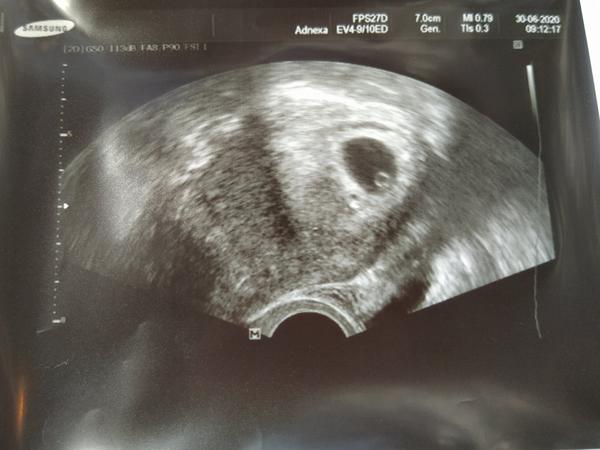

Ahoj holky, tak jsem teď odešla od Dr, folikuly měli 17mm prý se bál hyperstimilace, prý mám pcos. Teď dva měsíce pauza,další ms na krev na hormonální profil. Koncem srpna nebo září druhý pokus a dlouhý stimulační protokol, musíme prý syndrom rysknout